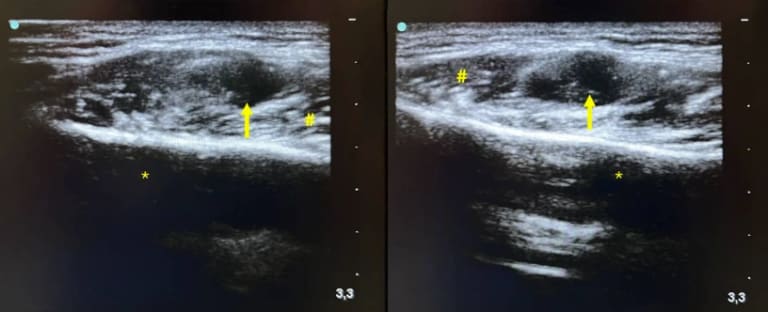

Abb. 3: Kontinuierliche intraoperative B‑Bild-Sonographie mit Darstellung der Raumforderung (Pfeil) von extraoral. Asterisk Corpus mandibulae, Raute M. masseter.